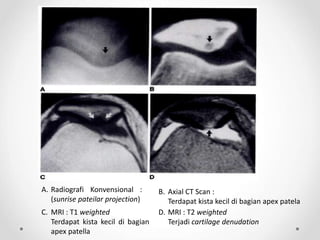

A. Radiografi Konvensional :

(sunrise pateilar projection)

B. Axial CT Scan :

Terdapat kista kecil di bagian apex patela

C. MRI : T1 weighted

Terdapat kista kecil di bagian

apex patella

D. MRI : T2 weighted

Terjadi cartilage denudation

A. Radiografi Konvensional: (sunrise pateilar projection) B. Axial CT Scan : Terdapat kista kecil di bagian apex patela C. MRI : T1 weighted Terdapat kista kecil di bagian apex patella D. MRI : T2 weighted Terjadi cartilage denudation